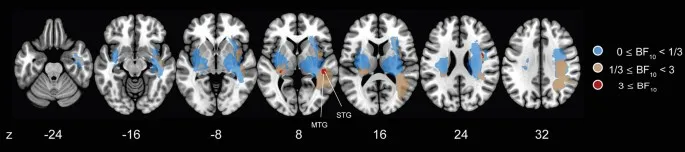

Байесовский вывод о связи поражения и дефицита (BLDI)

Чтобы infer статистическую association между location поражения и TDE, мы further выполнили Bayesian lesion-deficit inference (BLDI) с mapping Bayes factor. BLDI хорошо подходит, especially для исследований с малой мощностью/выборкой. Анализ выявил доказательства в пользу H1 (BF10 ≥ 3) в правой STG и MTG в соответствии с descriptive finding; однако вокселы в правой MOG и inferior parietal дольках (SMG и AG) оказались without evidence как для H0, так и для H1.